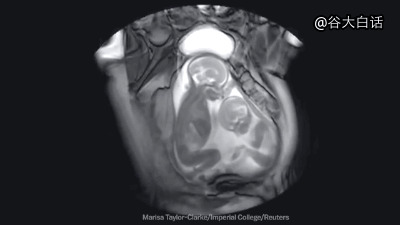

#爱你爱到骨头里#【MRI下诡异而奇妙的人体】这是一段用核磁共振成像技术制作的动态短片,将人类喝水、亲嘴、嘿咻、拉翔、生娃、说中文、说德文等日常活动展现得毫纤毕现、一览无遗。doge微猎奇,微暴,慎点。